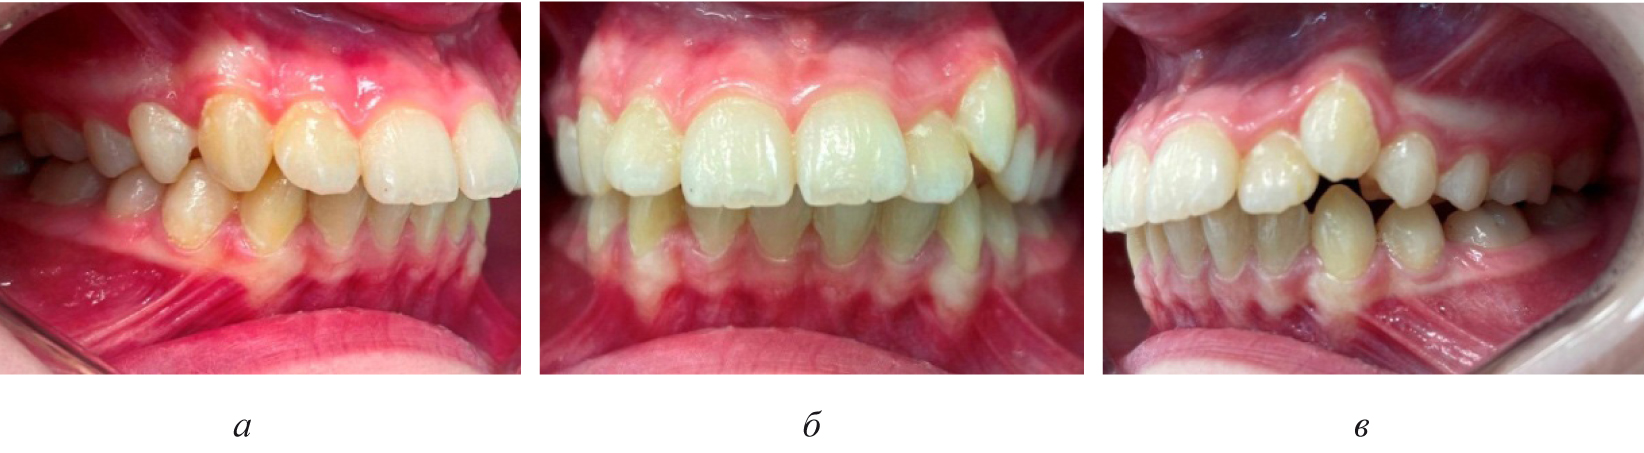

Смещение вторых постоянных моляров, как правило, было в меньшей степени выражено, чем отклонение от нормы других показателей биометрической диагностики. Достоверных различий при оценке положения вторых моляров на стороне ретенции и противоположной ей нами не отмечено (р ˃ 0,05). Смещение центральной точки дуги и изменения диагональных размеров резцово-клыковой и резцово-молярной диагонали способствовало смещению линии эстетического центра и нарушению смыкания пар зубов-антагонистов, которое было более выражено на стороне ретинированного зуба (рис. 3).

Рис. 3. Окклюзионные взаимоотношения справа (а), спереди (б) и слева (в) у пациента с односторонней ретенцией второго премоляра